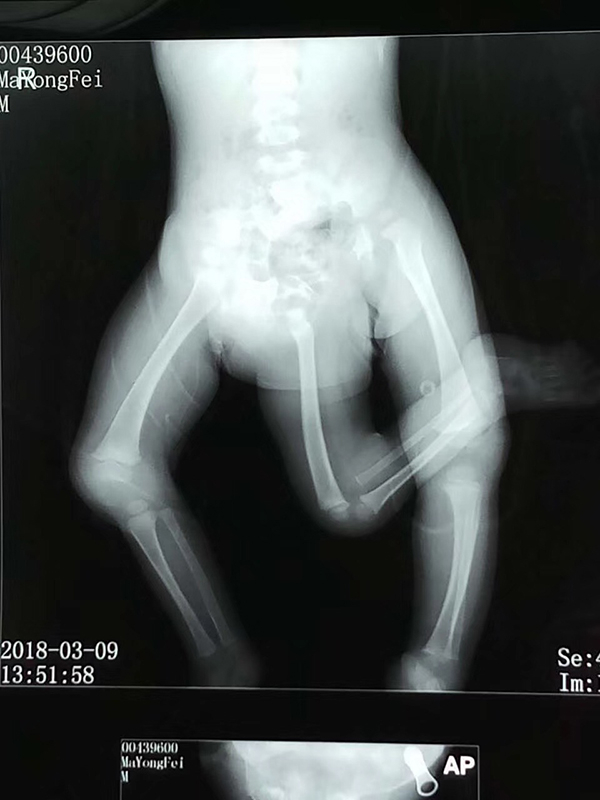

影像学检查。严晓慧供图

影像学检查。 严晓慧供图